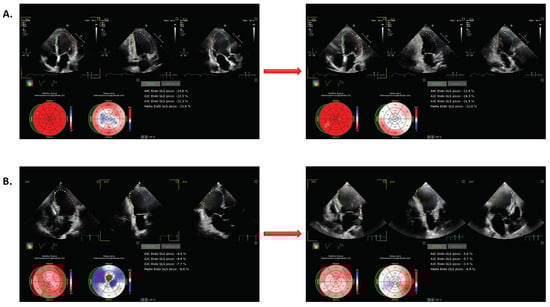

Significant changes in LVGLS were observed overall in response to higher-paced HRs (Figure 1). Thirty-four (76%) patients exhibited deteriorations in LVGLS equal to or greater than 10%; only one patient exhibited some degree of improvement (Figure S1). Figure 1 also documents changes in LVGLS in participants who did and who did not exhibit deterioration in response to an increasing HR. An example of patient with and without worsening of LVGLS is reported in Figure 2. The percentage of participants exhibiting LVGLS deterioration was higher among those managed with an ICD either with or without CRT, at 71% and 86%, respectively, than in participants with PM (57.1%). However, this difference did not achieve statistical significance (p = 0.28). As shown in Table 2, participants with deteriorating LVGLS were those with reduced LV function, as determined by baseline LVEF, LVGLS, and Tei index values.

Figure 2. Two examples of changes in LVGLS. The example in (A) documents improved LVGLS with increasing HR. The example in (B) documents a deterioration in LVGLS in response to increasing HR.